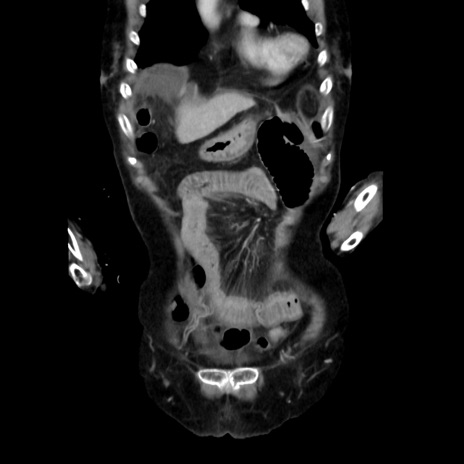

症例40(冠状断像)

【症例】90歳代女性

【主訴】腹痛・嘔吐

【現病歴】 食欲低下、嘔吐があり昨日他院受診。肺炎と診断され入院となる。入院後より腹部全体に圧痛あり。胃管留置され経過みていたが、症状持続するため、

当院転院となる。

【既往歴】胸椎圧迫骨折、胆石症

【身体所見】腹部:中央に激痛あり、圧痛あり、反跳痛不明

【データ】WBC 17100、CRP 18.82

横断像

他院CT